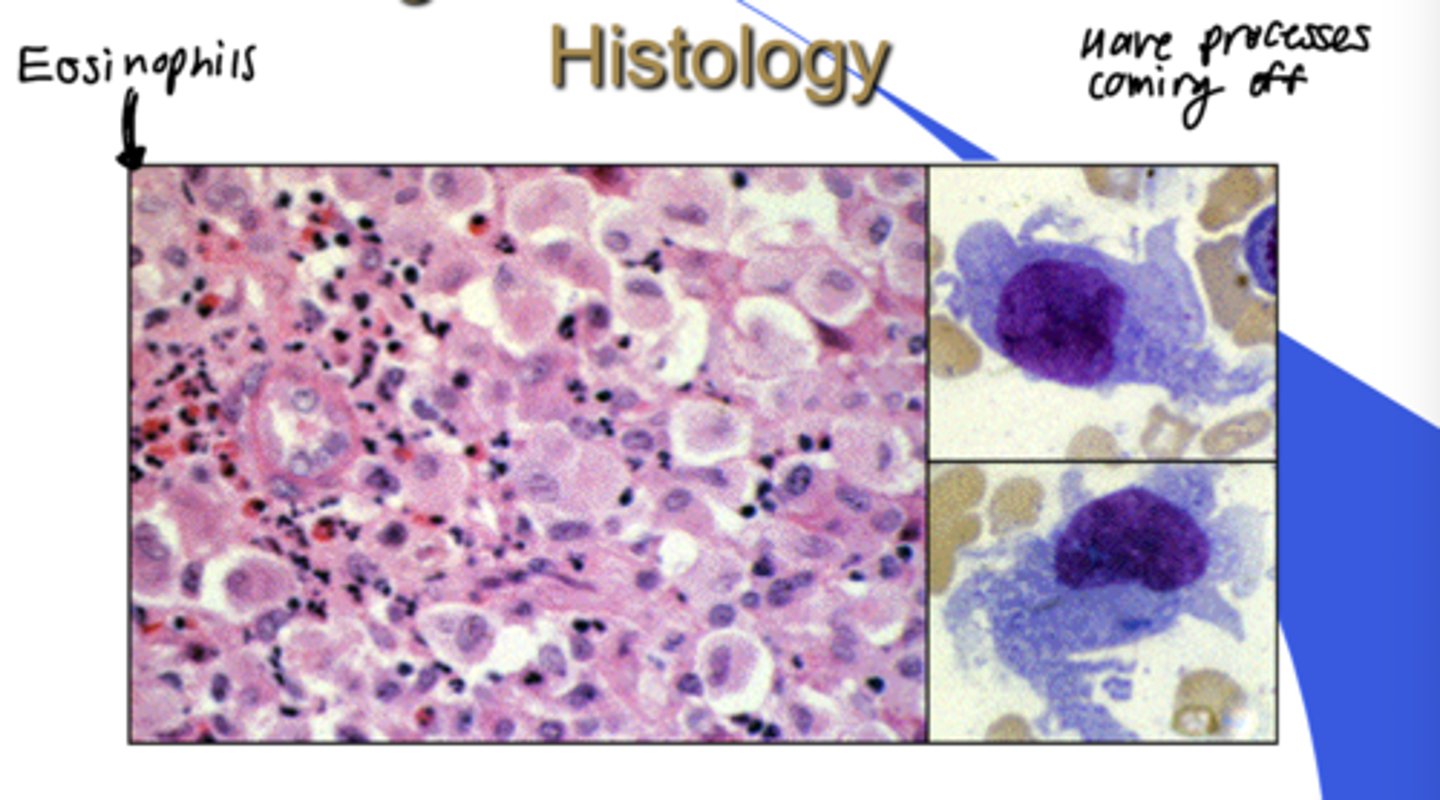

Langerhans cell disease - histology

Friable gingiva

= Fragile gingiva

- Can be localized (eosinophilic granuloma) or generalized